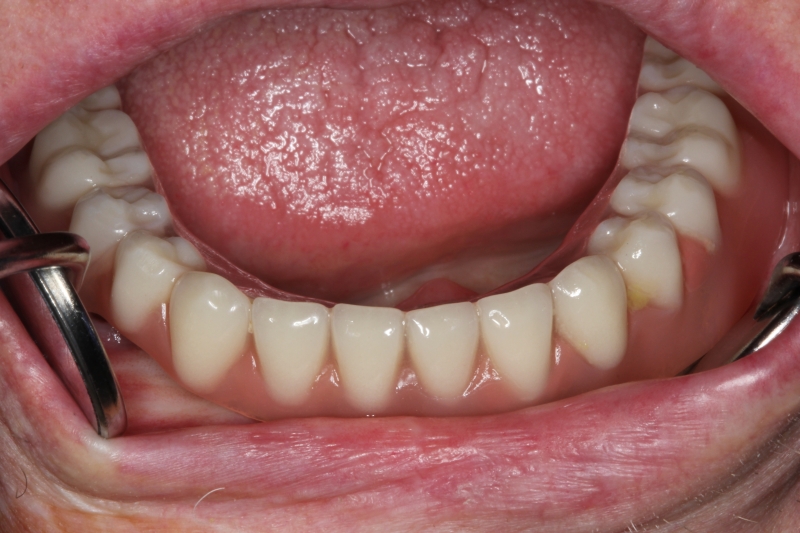

14/14 - Final prosthetic restoration

Block augmentation with maxresorb®, collprotect® membrane & autologous bone blocks - Prof. Dr. Dr. D. Rothamel